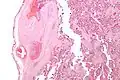

| Intermediate magnification micrograph of the placental disc showing a thrombosed fetal vein, as may be seen in fetal thrombotic vasculopathy. H&E stain. | |

Fetal thrombotic vasculopathy is a chronic disorder characterized by thrombosis in the fetus leading to vascular obliteration and hypoperfusion.

It can be diagnosed by histomorphologic examination of the placenta and is characterized by fetal vessel thrombosis and clustered fibrotic chorionic villi without blood vessels.